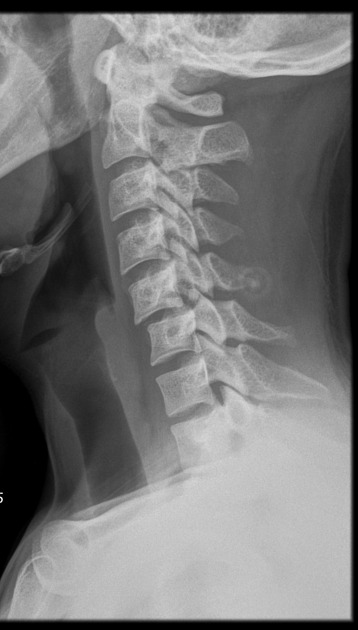

collapse of body from osteoporosis, kyphosis, trauma, or pathologic disease. Anterior wedge collapses, changing the shape to a wedge, best demoed on a lateral spine

spondylosis

neck stiffness from degeneration of disks, may affect the zygapophyseal jts and intervertebral foramen